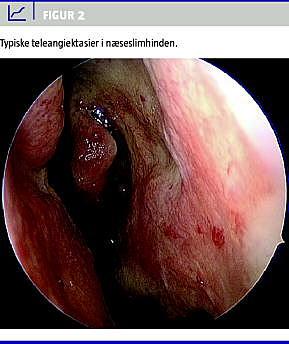

Epistaxis

Epistaxis af varierende hyppighed og intensitet forekommer hos 95% af patienterne [17], hvor hovedparten af HHT-patienterne debuterer med epistaxis i skolealderen. Hyppigheden og intensiteten af epistaxis øges hos mange af patienterne gennem en årrække, og kan hos op mod 40% blive svært invaliderende. Ved livskvalitetsundersøgelser har man påvist, at næseblødning er en væsentlig årsag til, at HHT-patienter oplever forringet livskvalitet [18, 19]. Epistaxis kan behandles med laser (f.eks argonlaser eller diodelaser), alternativt kan der foretages operation (septodermatoplastik) [20, 21], men nye telangiektaser vil typisk vokse frem, og efterhånden vil patienten opleve fornyede behandlingskrævende blødningsepisoder. Blødningen skyldes udvikling af telangiektaser i næseslimhinden (Figur 2 ), hvor telangiektaserne ofte er lokaliseret på septum og conchae. Med alderen bliver telangiektaserne ofte tyndvæggede og selv små traumer, f.eks nasale respirationsrelaterede, kan give anledning til blødning. En anden effektiv behandling er derfor temporær eller permanent reduktion af luftflowet gennem næsen. Ved invaliderende recidiverende blødning kan der anvendes kirurgisk lukning med Youngs procedure, hvor huden i næsen sys sammen [22]. Ulempen ved denne procedure er imidlertid, at nasal respiration herefter ikke er mulig med generende mundtørhed til følge.

2. Der påvises typiske telangiektaser (Figur 1 og 2)